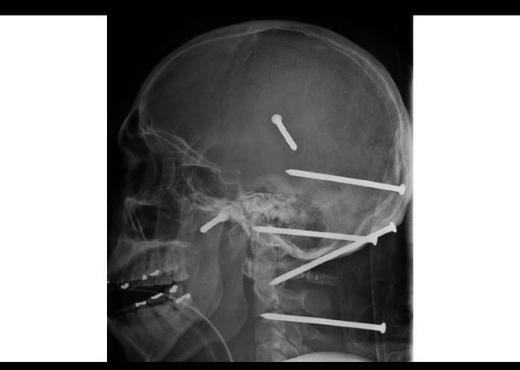

10. 2004'te yaşanan bir kaza sonucu inşaat işçisi Isidro Mejia'nın kafasına çivi makinesinden fırlayan altı çivi saplanmıştı. İşçi, geçirdiği ameliyatlar sonucu kurtarıldı.

2004'te yaşanan bir kaza sonucu inşaat işçisi Isidro Mejia'nın kafasına çivi makinesinden fırlayan altı çivi saplanmıştı. İşçi, geçirdiği ameliyatlar sonucu kurtarıldı.